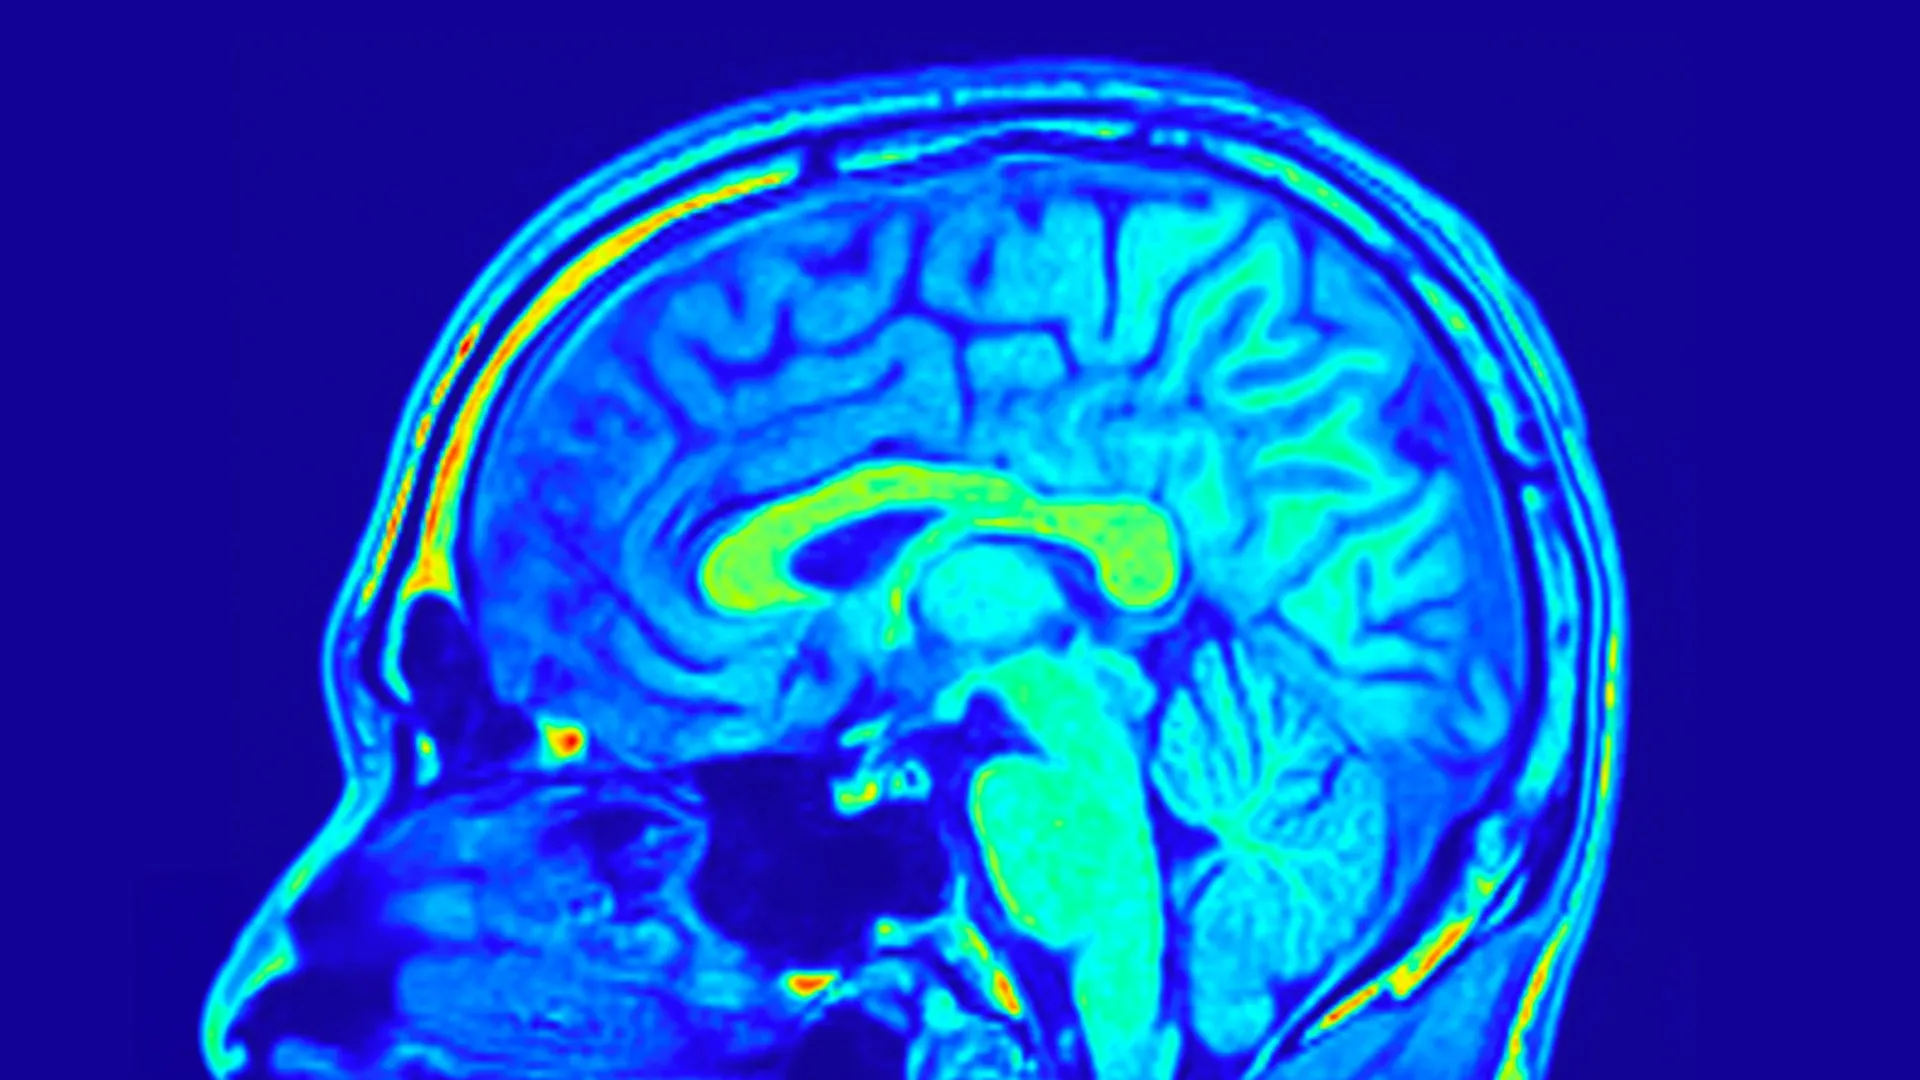

To systematically evaluate the impact of these interventions, the research team employed a multi-faceted approach. The severity of depressive symptoms was quantitatively assessed using the 24-item Hamilton Depression Scale (HAMD-24), a widely recognized and validated clinical instrument for measuring depression symptomatology. Beyond clinical assessments, the study delved into the biological underpinnings of depression and treatment response. Peripheral blood samples were meticulously collected to analyze key biochemical markers, and sophisticated magnetic resonance imaging (MRI) scans were performed to investigate potential alterations in brain structure and neurobiological function.

The advanced brain imaging data provided even more profound and nuanced insights into the differential effects of the treatments. The researchers identified that specific interconnected networks formed by distinct brain structures possessed the capacity to predict changes in depression symptom scores across both treatment groups. These neural networks, representing the intricate communication pathways and functional organization between different brain regions, offer a window into the underlying neural mechanisms of mood regulation.

More remarkably, the study uncovered that certain characteristic brain patterns, discernible through MRI, demonstrated predictive power exclusively in patients undergoing treatment with Yueju Pill. These predictive patterns were derived from measurements of sulcus depth and cortical thickness, which quantify the degree of folding of the cerebral cortex and the thickness of its outer layer, respectively. Both of these neuroanatomical features are intimately associated with brain development, cognitive processing, and overall neural function. Further detailed analysis revealed that the brain’s visual network, a system primarily responsible for processing visual information, played a particularly crucial role in foretelling improvements in both depressive symptoms and BDNF levels among participants who received Yueju Pill.